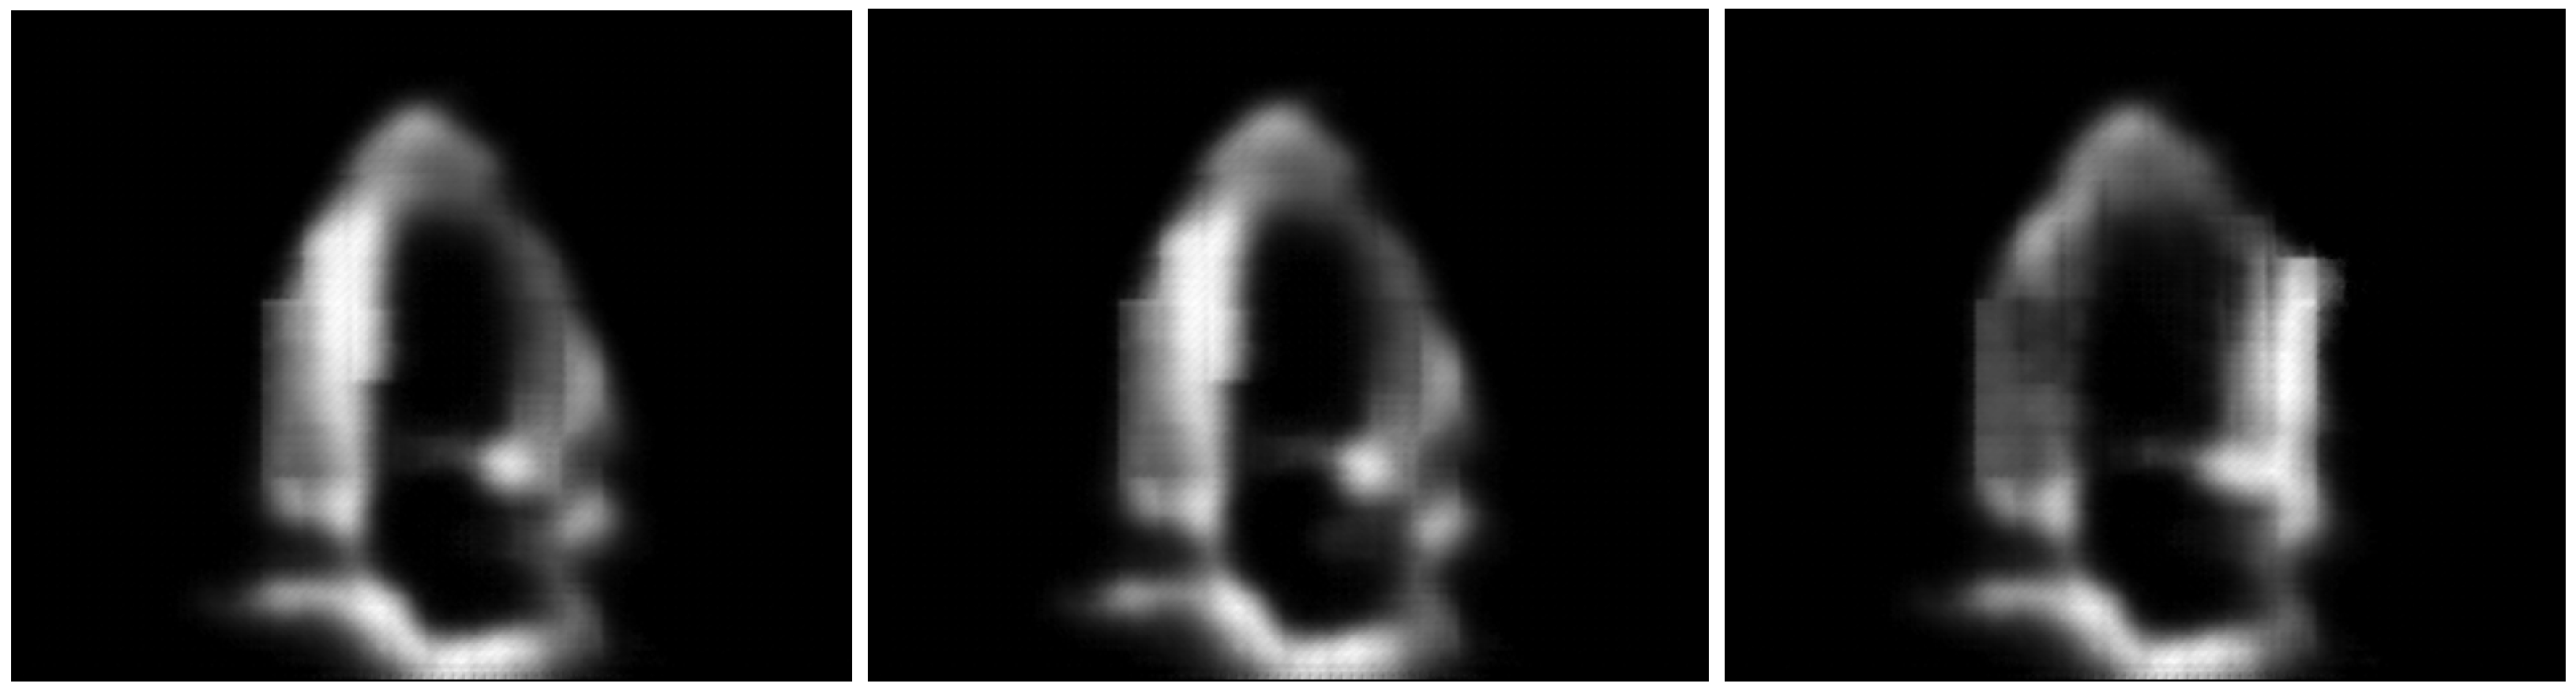

We further explore how style information can be used to generate synthetic data. Such data can be valuable for creating inputs conditioned by patient attributes, such as generating images with more textured walls. To achieve this, we leverage the known range of (since the constraint is enforced during training), and investigate style-based image generation. This involves adding Gaussian noise at various levels as described in Equation (7):

where controls the amount of noise injected into .

We then reconstruct the image using these style attributes. Randomly sampled reconstructions w.r.t. multiple (reusing the same sampled n) are illustrated in Figure 7, while Figure 8 illustrates reconstructions with multiple noise samplings and fixed . We observe that even with relatively high values, the reconstructions closely resemble the unaltered concepts, while the image textures are modified (with minimal changes to anatomical structures in terms of their shape or placement). This leads to the following observations:

- The model uses to decode semantic content, such as anatomical structures like chamber walls, blood pools, and valves, while is used to particularize local textures, shadows and speckles.

- With ConceptVAE, synthetic data can be generated by modifying only textures and speckles while retaining anatomical structures. This allows for the generation of novel samples that can serve as style augmentations without modifying the content, potentially enhancing the training performance of dense downstream models, such as those used for segmentation.

Figure 7.

Original images (left) displayed alongside reconstructions using with increasing levels of injected noise, . From the second column to the right, values are 0 (unaltered reconstruction), , and , respectively.

Figure 8.

Reconstructed images with unaltered (left) alongside three reconstructions with constant noise level . Each noisy reconstruction uses different noise, , as described in Equation (7).